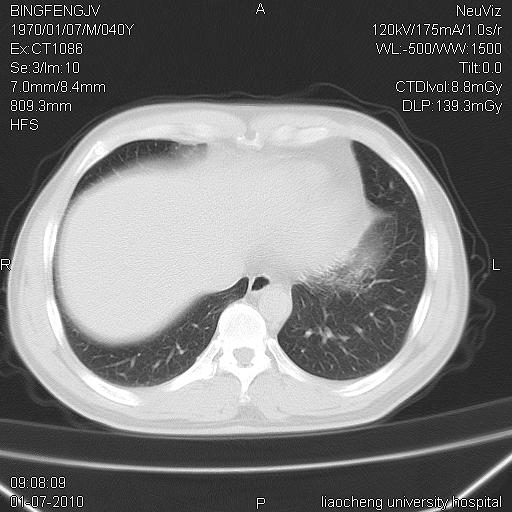

标题: CT23764B:男 40 肺部CT [打印本页]

标题: CT23764B:男 40 肺部CT

治疗2周后

考虑左肺上叶近胸膜下炎症并肺气囊形成。

炎症,大部吸收。